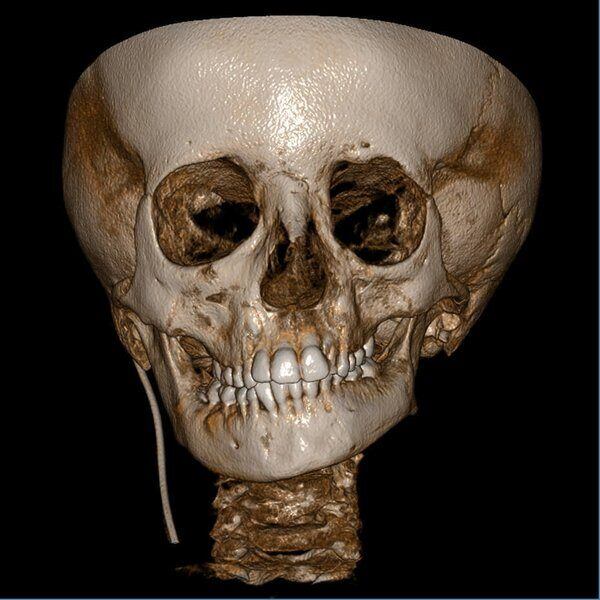

Acquisizione Maxiillofacciale per valutazione chirurgica di paziente con Sindrome di Goldenhar